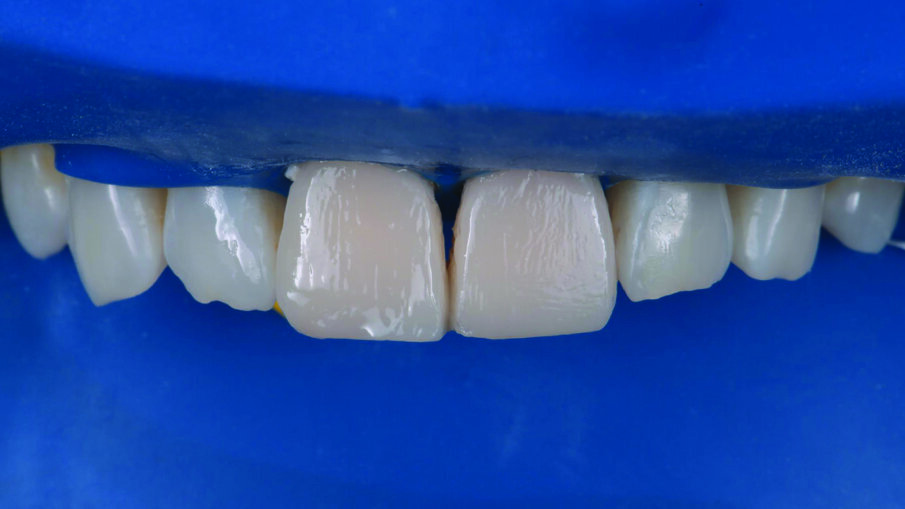

Appearance of the teeth after the first application of 3M™ Filtek™ Universal Restorative A1 shade. No additional body shades were needed (to mask sclerotic dentin) when using the Pink Opaquer.

Placement of the second and final layer of 3M™ Filtek™ Universal Restorative A1 shade.

Restorations after polishing using the 3M™ Sof-Lex™ Diamond Polishing System.